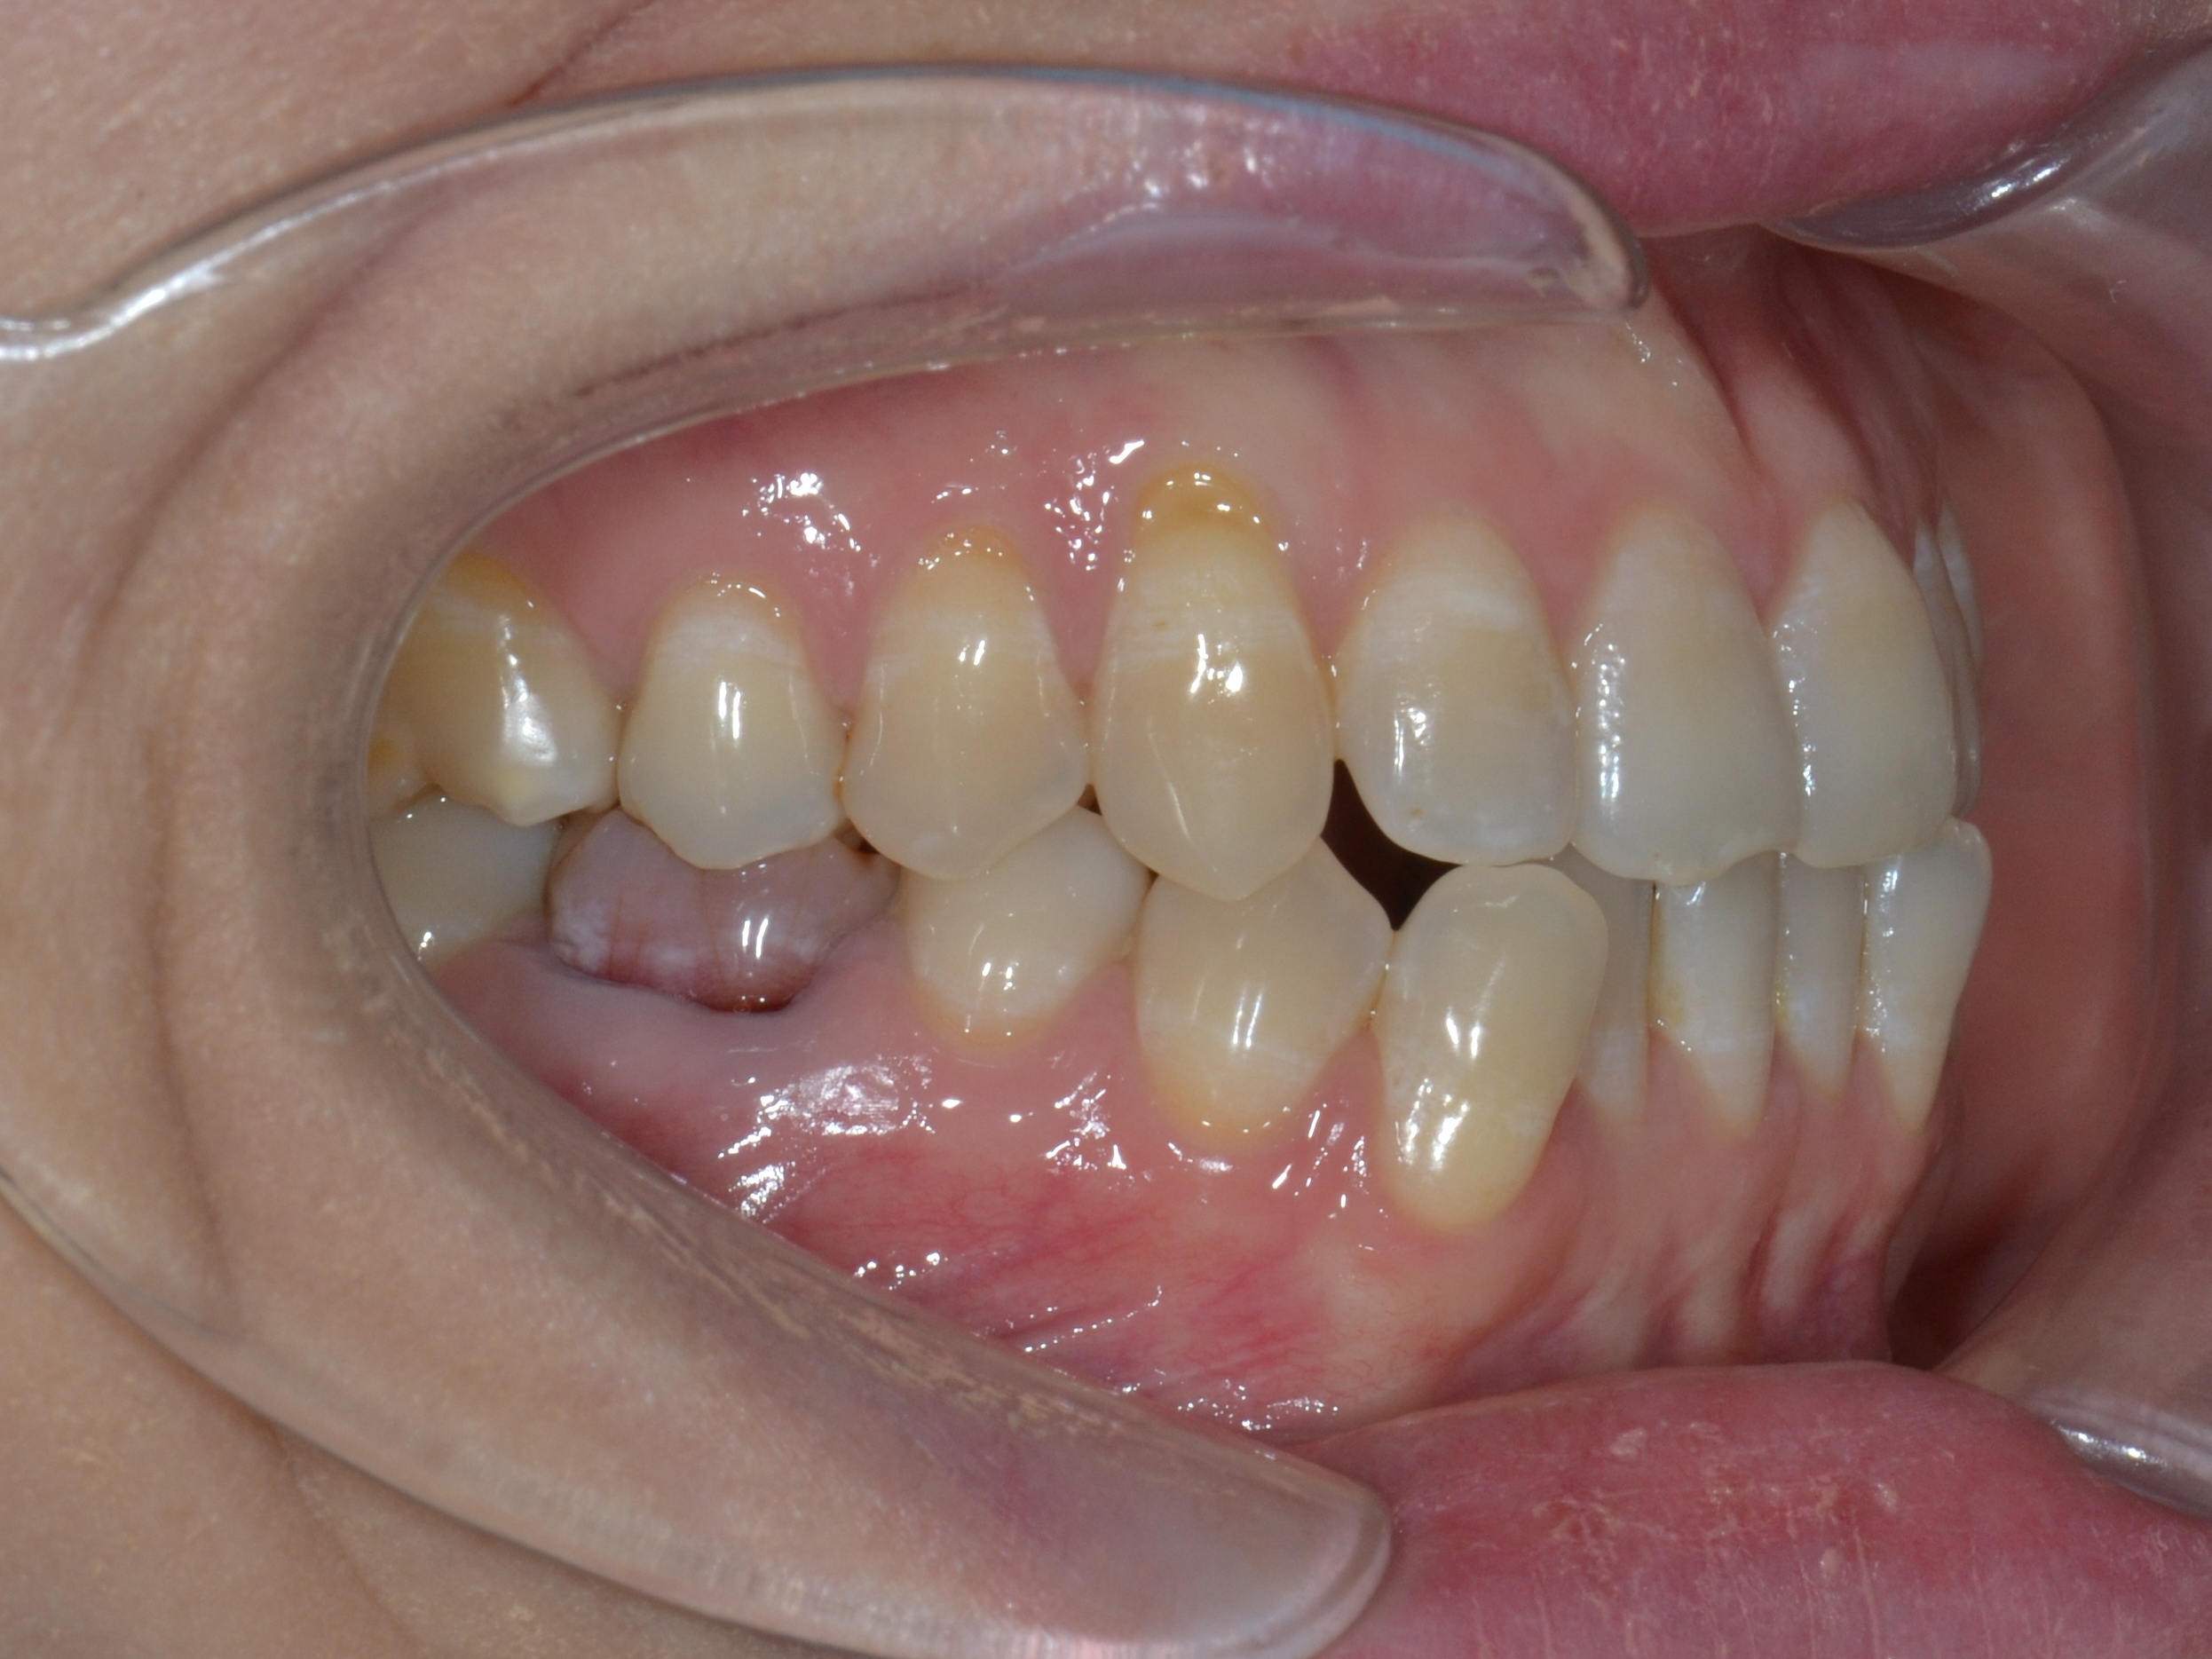

Выявленные проблемы

• Дистальная окклюзия ||(2)

• Глубокое резцовое соотношение

• Скученность фронтальных зубов

• Вестибулярное положение клыков

Брекет-система Ultra